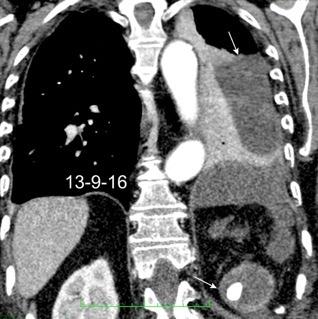

27. DERRAME PLEURAL IZQUIERDO. URINOMA

Enfermedad subdiafragmática Urinoma

Raro. Trasudado.

Orina en espacio pleural

Causas en 78 casos

Trauma……..66

Postcirugía 16

Obstrucción…21 aguda con cálculo e hidronefrosis..12

Freitas A et al. Pleural Effusion Secondary to Obstructive Uropathy: A Case of Urinothorax. Eur J Case Rep Intern Med. 2020/ Toubes ME et al. Urinothorax: a systematic review. J Thorac Dis 2017;

Hidronefrosis con cálculo ureteral